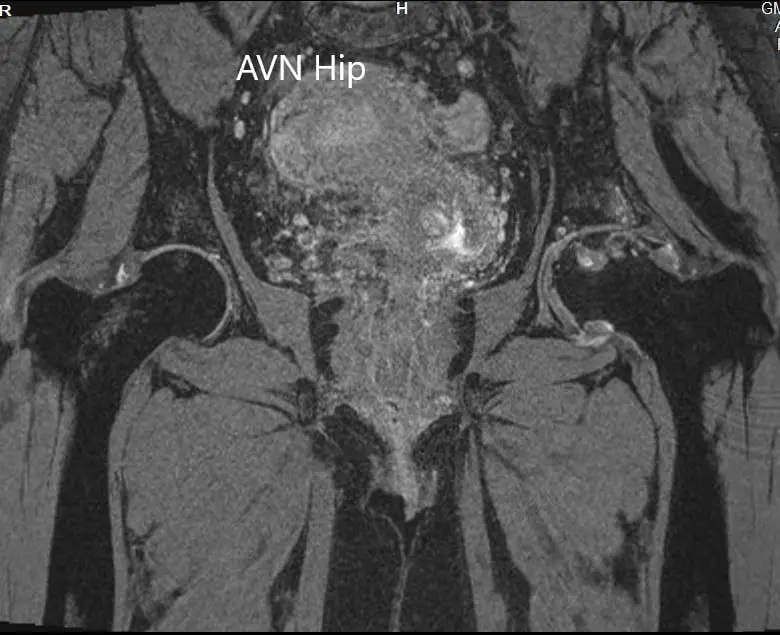

An MRI was obtained which showed altered signal intensity in both T1WI and T2WI. There was a subtle collapse of the left femoral head. A serpiginous hyperintense line was seen on T2WI demarcating an area of osteonecrosis in the left femoral head. This area involved the lateral and medial compartment and covered more than 50% of the surface area of the head.

Secondary osteoarthritic changes were visualized in the form of reduction of anterosuperior joint space and osteophyte formation. A small amount of fluid was seen in the joint cavity.

T2WI MRI image showing the coronal section.